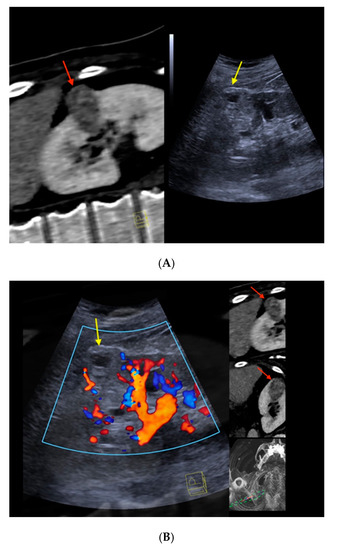

Figure 2 depicts the morphological correlates from CT/CEUS-fusion imaging of a clear-cell RCC. An overview of the findings from cross-sectional imaging (CT/MRI) and corresponding correlates by fusion imaging of the included renal liver lesions is depicted in Table 2.

Figure 2.

Real-time CT-/CEUS-fusion imaging of a complex renal cystic lesion. (A) Known complex renal cystic lesion with indicated septations and solid components in the right kidney from previous contrast-enhanced CT (left, red arrow) is displayed in a side-by-side mode with native B-mode (right, yellow arrow) by a high-end ultrasound system. (B) Additional Color Doppler did not reveal hypervascularization of the lesion (yellow arrow). The software interface of the ultrasound device showed four different images: the real-time Color Doppler image (left, maximized), the CT imaging dataset in sagittal (upper right) and axial (middle right) reformation (lesion marked by red arrows), and a real-time 3D navigation of the Fusion Imaging (lower right). (C) Contrast-enhanced ultrasound allowed for visualization of early arterial microperfusion of solid components of the lesion, implicating malignancy (left, maximized), (lesion marked by red arrows in corresponding CT images). The patient underwent partial nephrectomy. Histopathology, finally, revealed underlying clear-cell renal cell carcinoma.